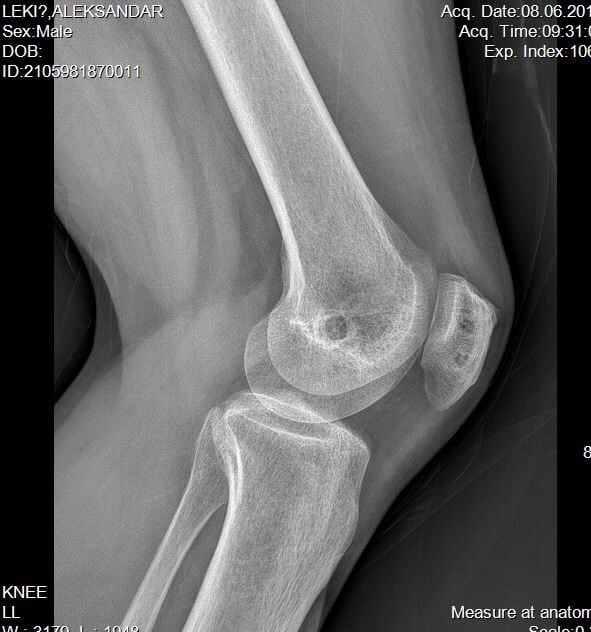

Za adekvatan pregled kolena i čašice, pored testiranje potrebni su, i za prvu luksaciju nekad i dovoljni, rtg snimci a nekad je za prvu ali češće za ponavljajuće luksacija čašice neophodan i MR pregled kolena.